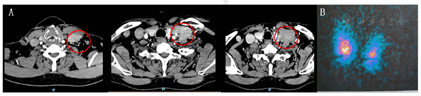

影像学检查:我院甲状腺及颈部淋巴结彩超检查:左侧颈部Ⅲ区探及大小约7.8 mm×3.2 mm。淋巴结回声,左侧颈部可见大小约4.5 cm×5.0 cm稍高回声结节,内可见斑片样高回声。双侧甲状腺及右侧颈部淋巴结未见确切异常。颈部增强CT检查:左侧锁骨上窝可见软组织密度影,大小约4.1 cm×3.3 cm,提示神经源性肿瘤?双侧甲状腺未见异常(图2A)。131碘化钠核素扫描检查:双侧甲状腺腺体稍肿大,两叶腺体内放射性分布大致均匀,未见异常放射性浓度及稀疏缺损区,提示甲状腺轻度弥漫性肿大(图2B)。甲状腺摄131I率测定:2小时摄碘率4.6%(10%~30%),6小时摄碘率9.8%(20%~50%),24小时摄碘率19.6%(35%-60%)。左侧锁骨上窝肿块穿刺活检提示:甲状腺乳头状癌。